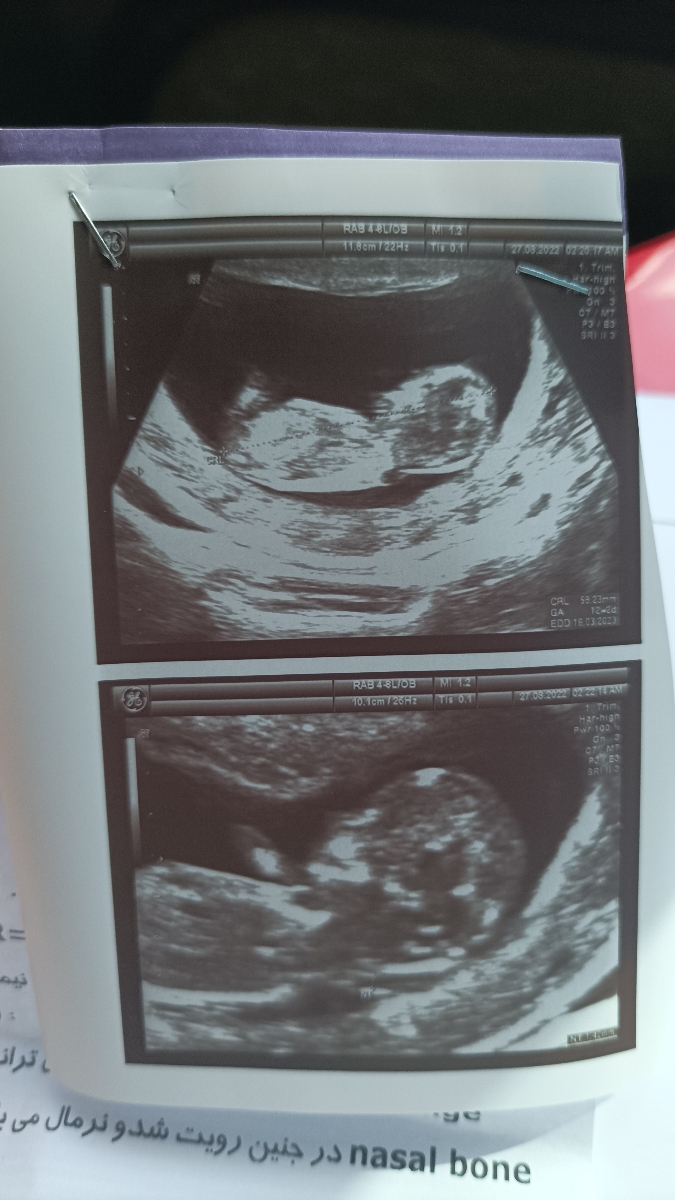

خیلی بالاس ان تی

ان تی تا 2 نرماله این 7هس

کیستیک هیگروما یک رشد غیر طبیعی بافت است که معمولا در سر و گردن جنین در سونوگرافی مشخص میشود که میتواند در غربالگری سه ماهه اول بارداری مشخص شود که با افزایش NT (ضخامت پشت گردن جنین) و عدم دیده شدن استخوان بینی می تواند همراه باشد.

کیستیک هیگروما در واقع کیسه ای پر از مایع ناشی از انسداد در سیستم لنفاوی می باشد که تقریبا نیمی از جنین هایی که اختلالات کروموزومی دارند از این کیست رنج می برند.

علت مهم بروز کیستیک هیگروما در واقع اختلالات ژنتیکی مخصوصا اختلال کروموزومی می باشد که شایع ترین اختلال کروموزمی همراه با کیستیک هیگروما سندرم ترنر و یا تریزومی سیزده و هجده و بیست و یک می باشد. در برخی اختلالات کروموزومی دیگر نیز ممکن است دیده شود. از عوامل محیطی علت بروز این مورد می توان به عفونت های ویروسی ، مصرف مواد مخدر یا الکل اشاره کرد.

این اختلال در جنین می تواند همراه آنومالی های قلبی (ناهنجاری های مادرزادی قلبی) و مشکلات دستگاه ادراری – تناسلی و سیستم عصبی مرکزی مغز و نخاع همراه باشد.

در صورت بروز این یافته در سونوگرافی توصیه به بررسی کروموزومی در جنین می شود و در صورت سقط شدن جنین قبل از بررسی کروموزومی، بررسی کروموزومی روی جنین سقط شده توصیه می شود.

دکتر برای این خانم احتمال کیسیک هیگروما داده

عدد nt خیلی بالاس حتما بگو آزمایش خونشو بده